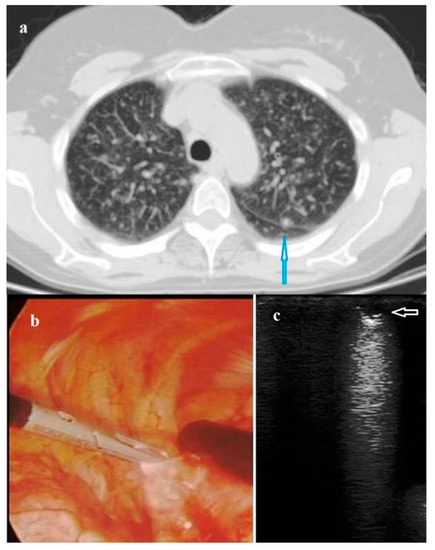

According to the ILU pattern, 125 (95.42%) nodules were classified as hypoechoic and six (4.58%) as hyperechoic. Among the hypoechoic nodules, 37 (28.24%) had intralesional hyperechoic spots. Benign nodules were in the vast majority of cases (94.12%) hypoechoic, with internal hyperechoic spots only in 38.24% of cases; they had regular rounded shape in all cases, and no jagged margins in 91.18% of cases. Malignant nodules were mostly hypoechoic (96.67% of cases) with jagged margins (68.33%). Internal hyperechoic spots were found only in the 21.65% of cases. A regular rounded shape was observed in roughly the half (53.33%) of cases (Figure 2). Metastases were mostly hypoechoic (94.59%), with jagged margins (100.00%). Internal hyperechoic spots were seldom assessed (29.73%) (Table 3).

Figure 2. (a) Intraoperative lung ultrasound (ILU) scan showing a hyperechoic pulmonary nodule (white arrow) with a regular rounded shape and well-defined margin. The final histological diagnosis was pulmonary hamartoma. (b) Intraoperative lung ultrasound (ILU) scan showing a hypoechoic nodule (blue arrow) with irregular shape and jagged margin. The final histological diagnosis was pulmonary adenocarcinoma.